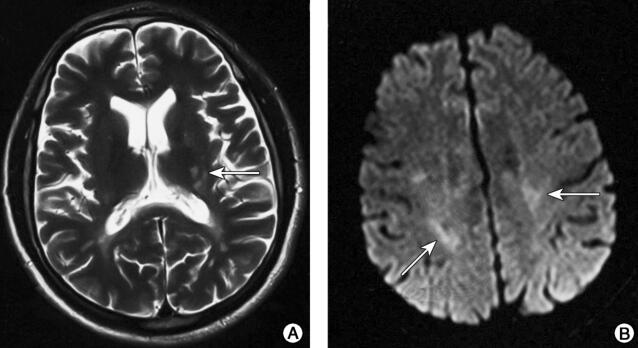

①头颅MRI(2015-12-30)(图1):双侧额叶深面、侧脑室旁、半卵圆中心白质内多发点状稍长T1稍长T2信号,FLAIR高信号,部分病变DWI高信号,增强扫描左侧基底节区、侧脑室旁见数个斑点状强化。②头颅MRI(2016-9-14)(图2):双侧基底节、侧脑室旁、半卵圆中心见多发点片状长T1长T2信号,部分与脑室垂直,DWI呈稍高信号;增强扫描未见异常强化;MRS示较大病灶处Cho峰轻度升高、NAA峰轻度下降,未见高灌注。③头颅MRI(2017-6-1):双侧基底节、侧脑室旁、半卵圆中心见多发点片状长T1长T2信号,部分与脑室垂直,DWI低信号,与2016年9月14日片比较未发现新发病灶。④颈胸椎MRI(2015-12-30)(图3):C3~C5脊髓稍长T1稍长T2信号,增强扫描呈环形强化。

图1 头颅及脊髓MRI(2015-12-30)检查结果

注:A.双侧额叶深面、侧脑室旁、半卵圆中心白质内可见多发点状稍长T2信号(箭头);B.双侧额顶叶DWI高信号(箭头);C.增强扫描示左侧基底节区、侧脑室旁见数个斑点状强化(箭头);D.双侧侧脑室旁FLAIR高信号